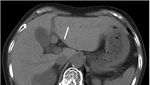

Jakarta - Dokter di Jepang menemukan jarum jahit 3 cm di hati nenek 81 tahun saat cek pencernaan. Ternyata jarum tersebut bisa masuk ke dalam tubuh lewat ini.

Penampakan Jarum Jahit Nyangkut di Liver Nenek Umur 81, Masuk Lewat Mana?

Jarum jahit sepanjang sekitar 3 cm berhasil diangkat melalui operasi laparoskopi. Pasien pulih dengan baik dan dipulangkan empat hari setelah operasi tanpa komplikasi. (Foto: Journal of Surgical Case Reports)